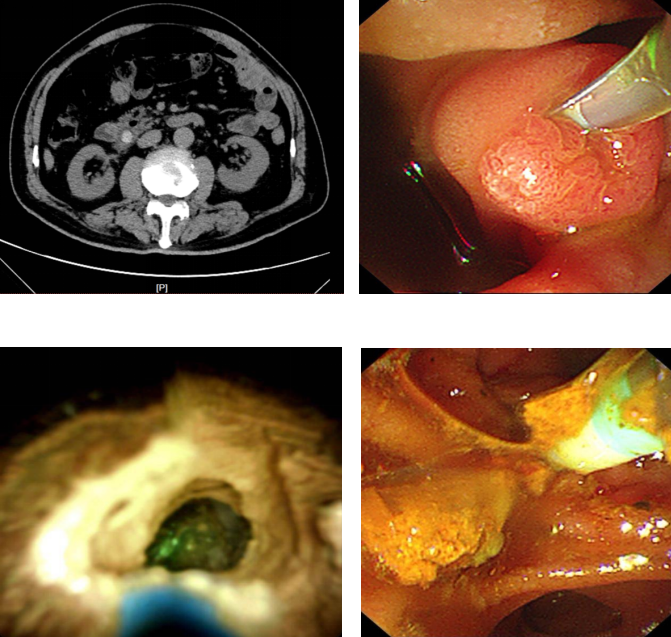

近日,75 岁的马先生(化姓)因饮酒后突发剧烈呕吐,检查发现胆总管结石堵塞引发急性化脓性胆管炎,同时合并胰腺炎,病情危急。东南大学附属中大医院消化内科主任冯亚东主任医师团队紧急实施微创手术,运用数字胆道镜辅助无射线内镜逆行胰胆管造影术(ERCP)治疗胆管结石,通过十二指肠镜,借助先进的胆道子镜系统精确定位结石,采用钬激光将结石粉碎取出,并植入支架疏通胆道。

据介绍,冯亚东主任医师团队最早于 2019 年在江苏省内率先开展了新型胆道镜直视下无射线 ERCP 微创手术,这种数字胆道镜的应用,可有效弥补传统 ERCP 的不足,其拥有双通道操作系统及高质量成像技术,可直接观察、定位和治疗胆管结石,同时可联合液电碎石和激光碎石等碎石技术治疗困难结石,为胆管结石的诊疗提供了新手段。